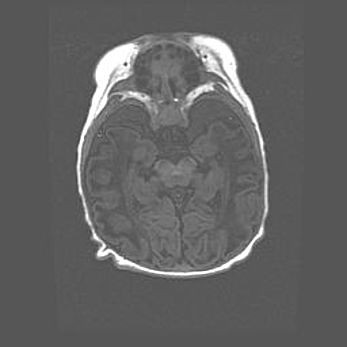

Наружная гидроцефалия с возможной атрофией височных областей.

Возраст: 28 дней

Вес: 3670 г

Пол: мужской

Окружность головы: 38 см

Срок гестации: 40 недель

Гидроцефалия головного мозга у новорожденных – это заболевание, которое характеризуется скоплением избыточного количества спинномозговой жидкости в желудочковой системе головного мозга в результате затруднения её перемещения от места выработки к месту поглощения в кровеносную систему или вследствие нарушения абсорбции. При открытой наружной форме гидроцефалии у новорожденных расширяются и переполняются субарахноидные пространства.

При нормотензивных  формах,  которые,  как  правило,  являются  следствием  перенесенных ишемических  повреждений  паренхимы  мозга,  возможно  сочетание микроцефалии  с нормотензивной гидроцефалией. В основе данных изменений лежит атрофия больших полушарий с преимущественной  локализацией  в  лобно-височных  областях.